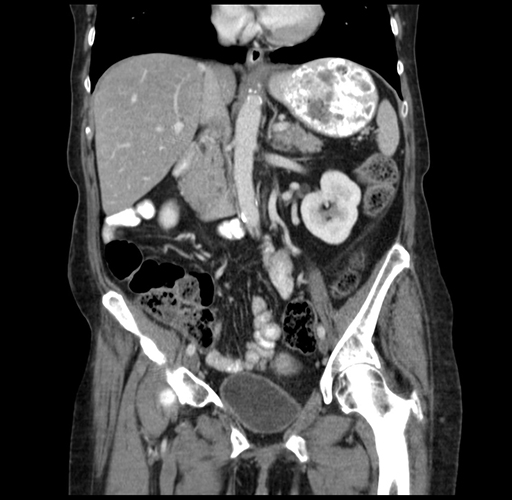

Pre-Chemo: Coronal Venous

Coronal Venous